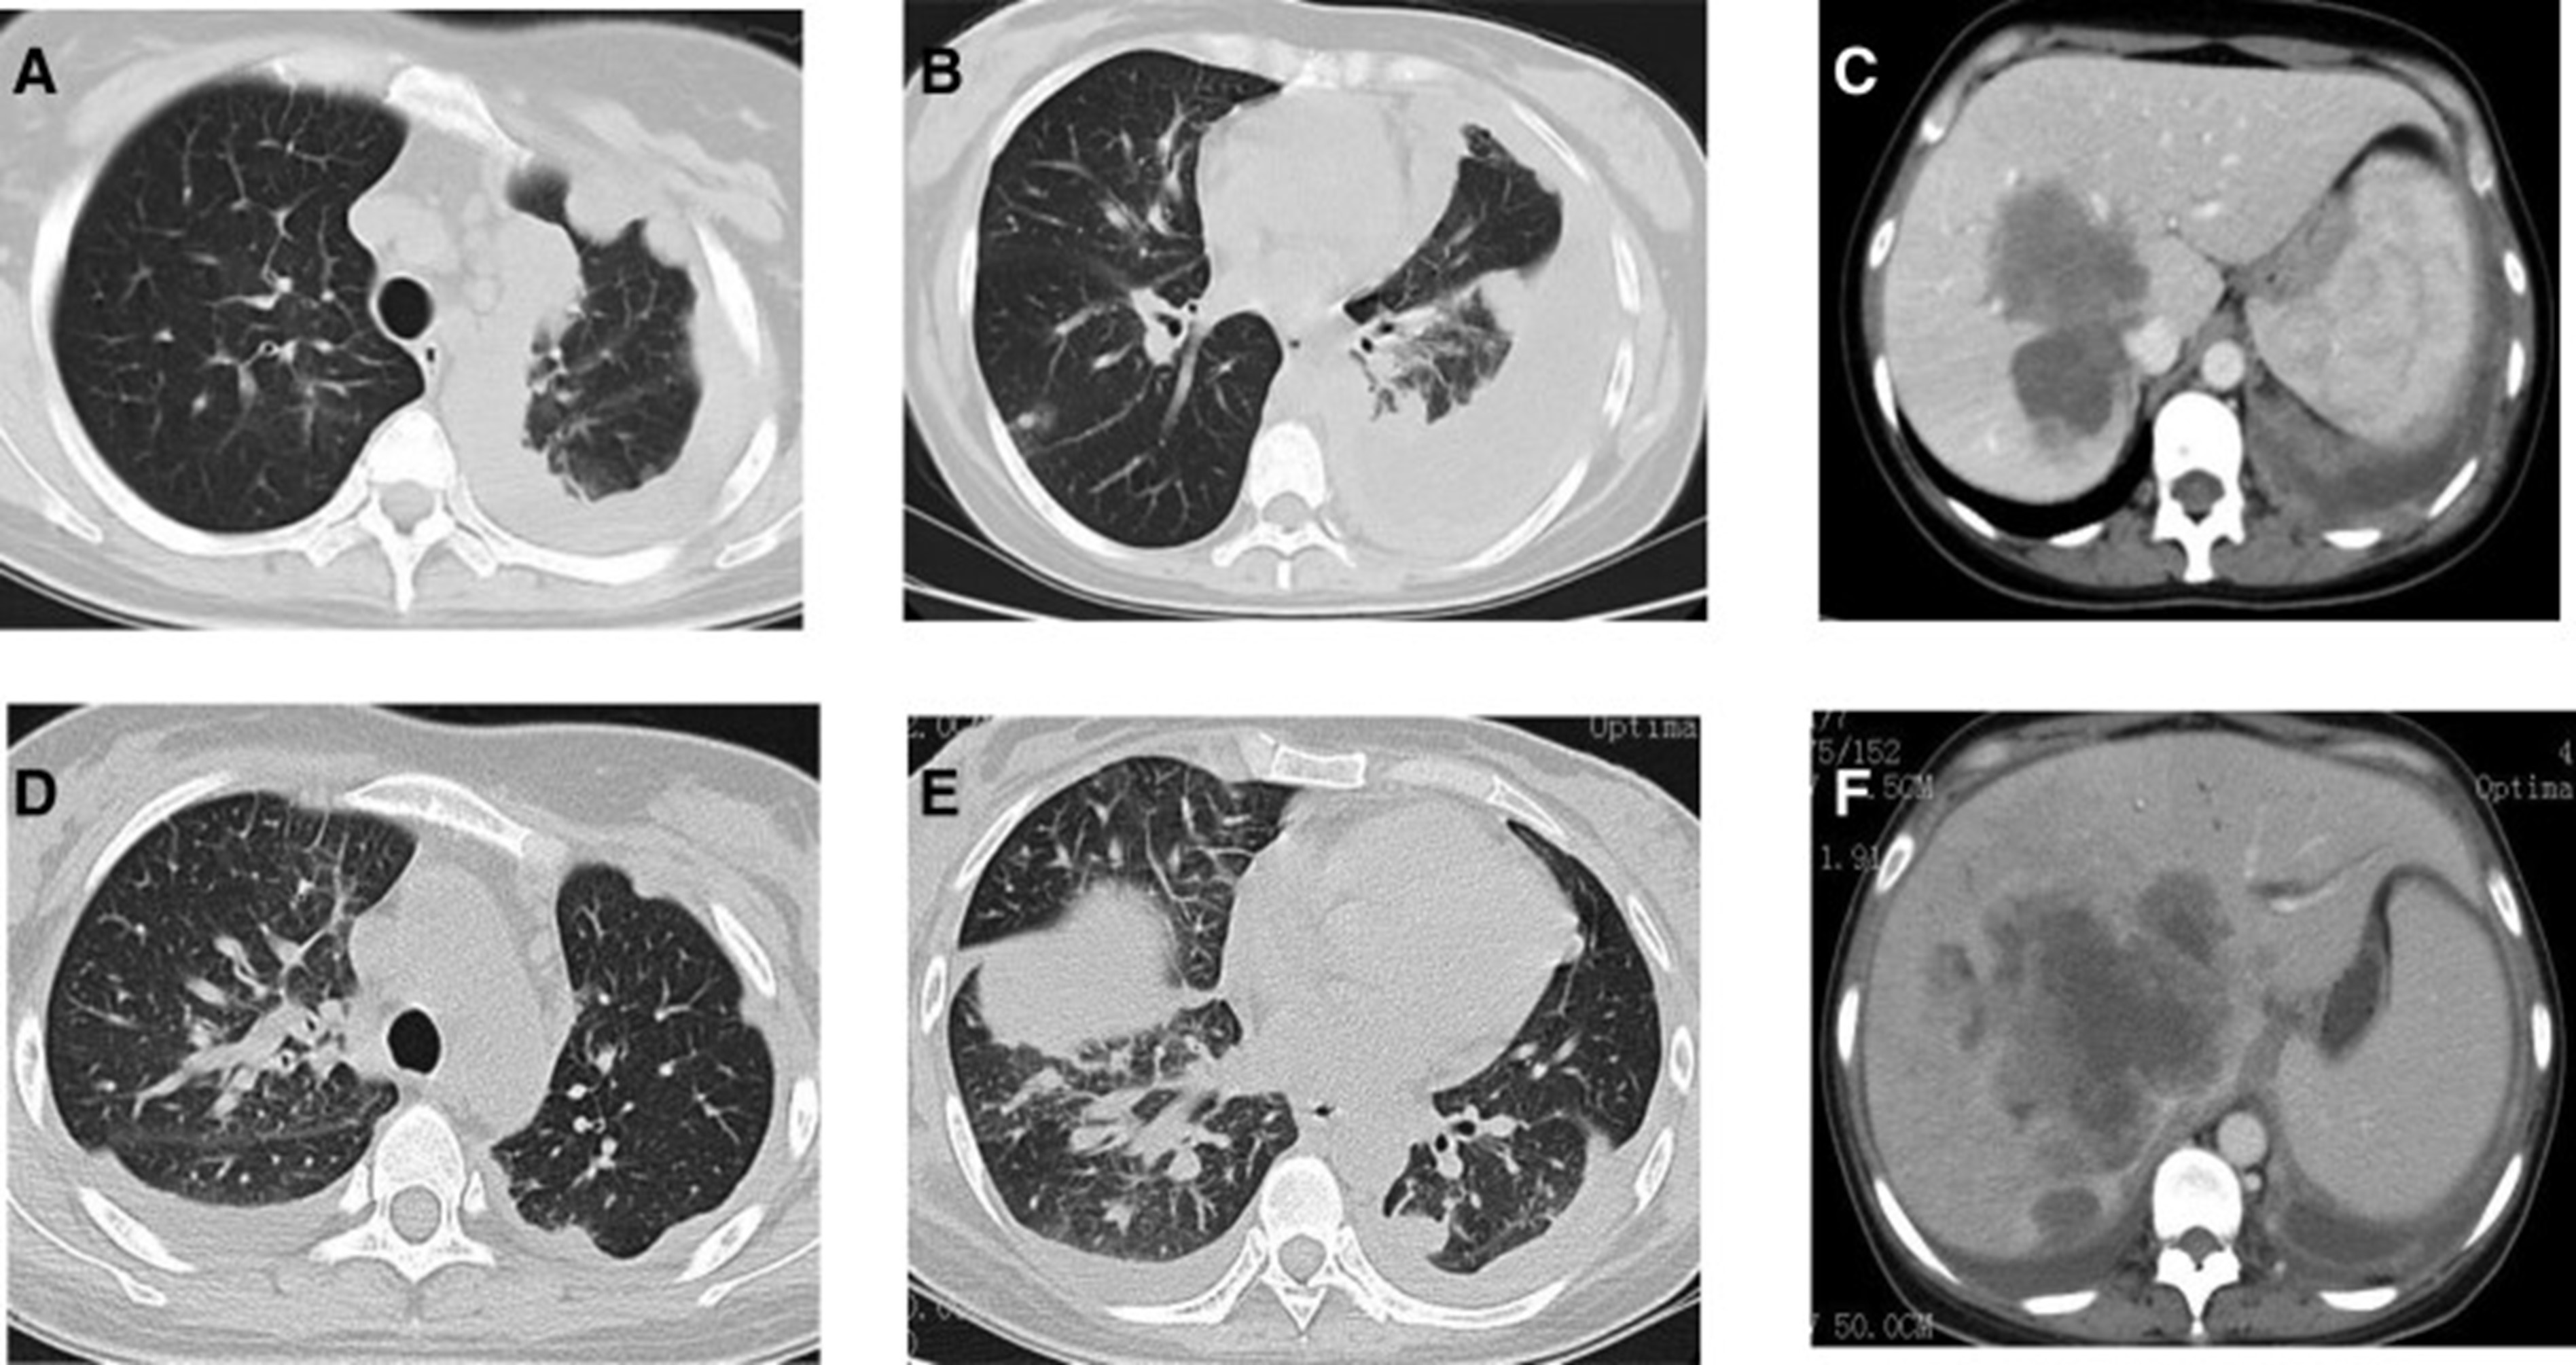

2020年5月1日,患者开始口服艾乐替尼靶向药物进行治疗,2020年6月25日复查,确定治疗效果为PR(部分有效)(根据RECIST1.1)显示肺病灶和肝转移灶明显减少(图1)。(图 3D-F)。2020 年 8 月 27 日复查确定治疗效果为疾病进展(PD, progressive disease),根据 RECIST1.1显示肝脏病变变大(图 1)(图 4A-D)。进行了第二次肝活检,随后的病理学显示“(肝)低分化癌,结合免疫组织化学分析考虑肺腺癌转移”。组织活检进行了第二轮基因检测,结果显示“BRAFV600E 14.79%,EML 4-ALK fusion 14.47%”(图 1)(图 5)。2020年9月20日,对患者我以为用恩沙替尼联合达拉非尼靶向治疗。治疗开始后,患者出现明显发热、寒战、乏力和厌食。期间患者左侧出现大量胸腔积液,胸腔积液中脱落细胞为“非典型细胞,考虑为腺癌”。随后,该患者接受了 1 次胸腔内铂输注。

和 2020 年 8 月.jpg)

图 5:2020 年 6 月(A 和 B)和 2020 年 8 月(C 和 D)的 CT 扫描。CT = 计算机断层扫描。

1个月后复查显示肺部和肝内病变进展(图1)。(图 6A-C)(根据RECIST1.1),她的抗肿瘤治疗改为“培姆曲塞加卡铂和贝伐单抗”的治疗一个周期。2020年12月至2021年1月,再次改变患者的治疗方案,这次改为“劳拉替尼联合达拉非尼”靶向治疗。使用 PD 联合胸部和腹部 CT 评估疗效(图 1)。(图 6D-F)(根据 RECIST1.1)。患者无法耐受化疗、靶向治疗、IO 治疗或任何其他积极的抗肿瘤治疗。这是因为患者的一般情况较差,包括发烧、腹痛和胆红素水平升高等症状。随后,给予患者静脉营养、镇痛等对症支持治疗。患者于 2021 年 2 月 4 日去世,总生存期(OS)为 10 个月。